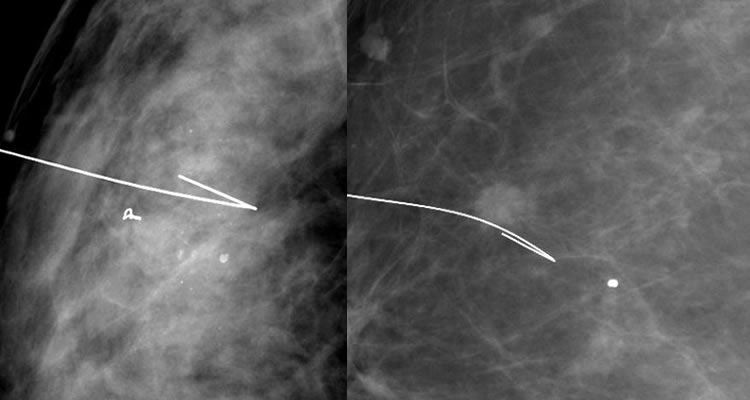

Il s'agit d'une piqûre du sein (de même désagrément qu'une piqûre dans le bras). Quand le radiologue a vérifié par mammographie la position de l'aiguille fine, il enlève l'aiguille, en laissant le repère en place. C'est ce fil que l'on appelle un guide ou harpon .

1 2 3

1 Repérage d'un clip post-biopsies 2 Repérage d'une masse 3 Contrôle per-opératoire de la pièce de tumorectomie (le repère est bien dans la zone d'exérèse)